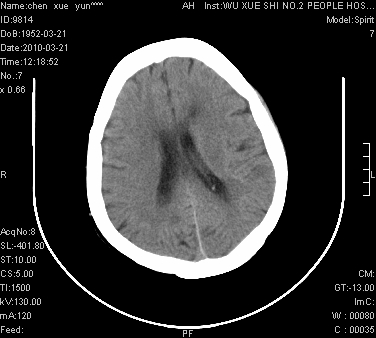

性别:不详;年龄:58岁;病史:不详。

ct表现:1、右侧额颞叶深部不规则钙化密度团块,呈弯曲条带状,占位效应不明显,考虑少枝胶质细胞瘤可能性大于血管瘤。2、右枕叶大片不规则低密度影,密度近似于脑脊液,右侧侧脑室后角及三角区扩张,考虑为陈旧性脑梗塞。

讨论:1、这个病灶的钙化有点像脑回样钙化,因此我最初考虑颅面血管瘤病(sturge-weber综合征),但是查阅了我们网站上的几个颅面血管瘤病病例,钙化均位于脑实质表面,沿脑回分布,而这例病灶位置较深,因此可以否定“颅面血管瘤病”这个诊断。

2、卜一会员曾经说过:少枝胶质细胞瘤的典型征象为弯曲条带状钙化,可作为定性的可靠征象(http://www.radida.com/news_view.asp?id=5150)

3、血管瘤也可以出现弯曲条带状钙化,但血管瘤多数出现“负占位”效应,即病灶周围的脑室、脑池及脑沟不是受压变窄,而是局限性的增宽。